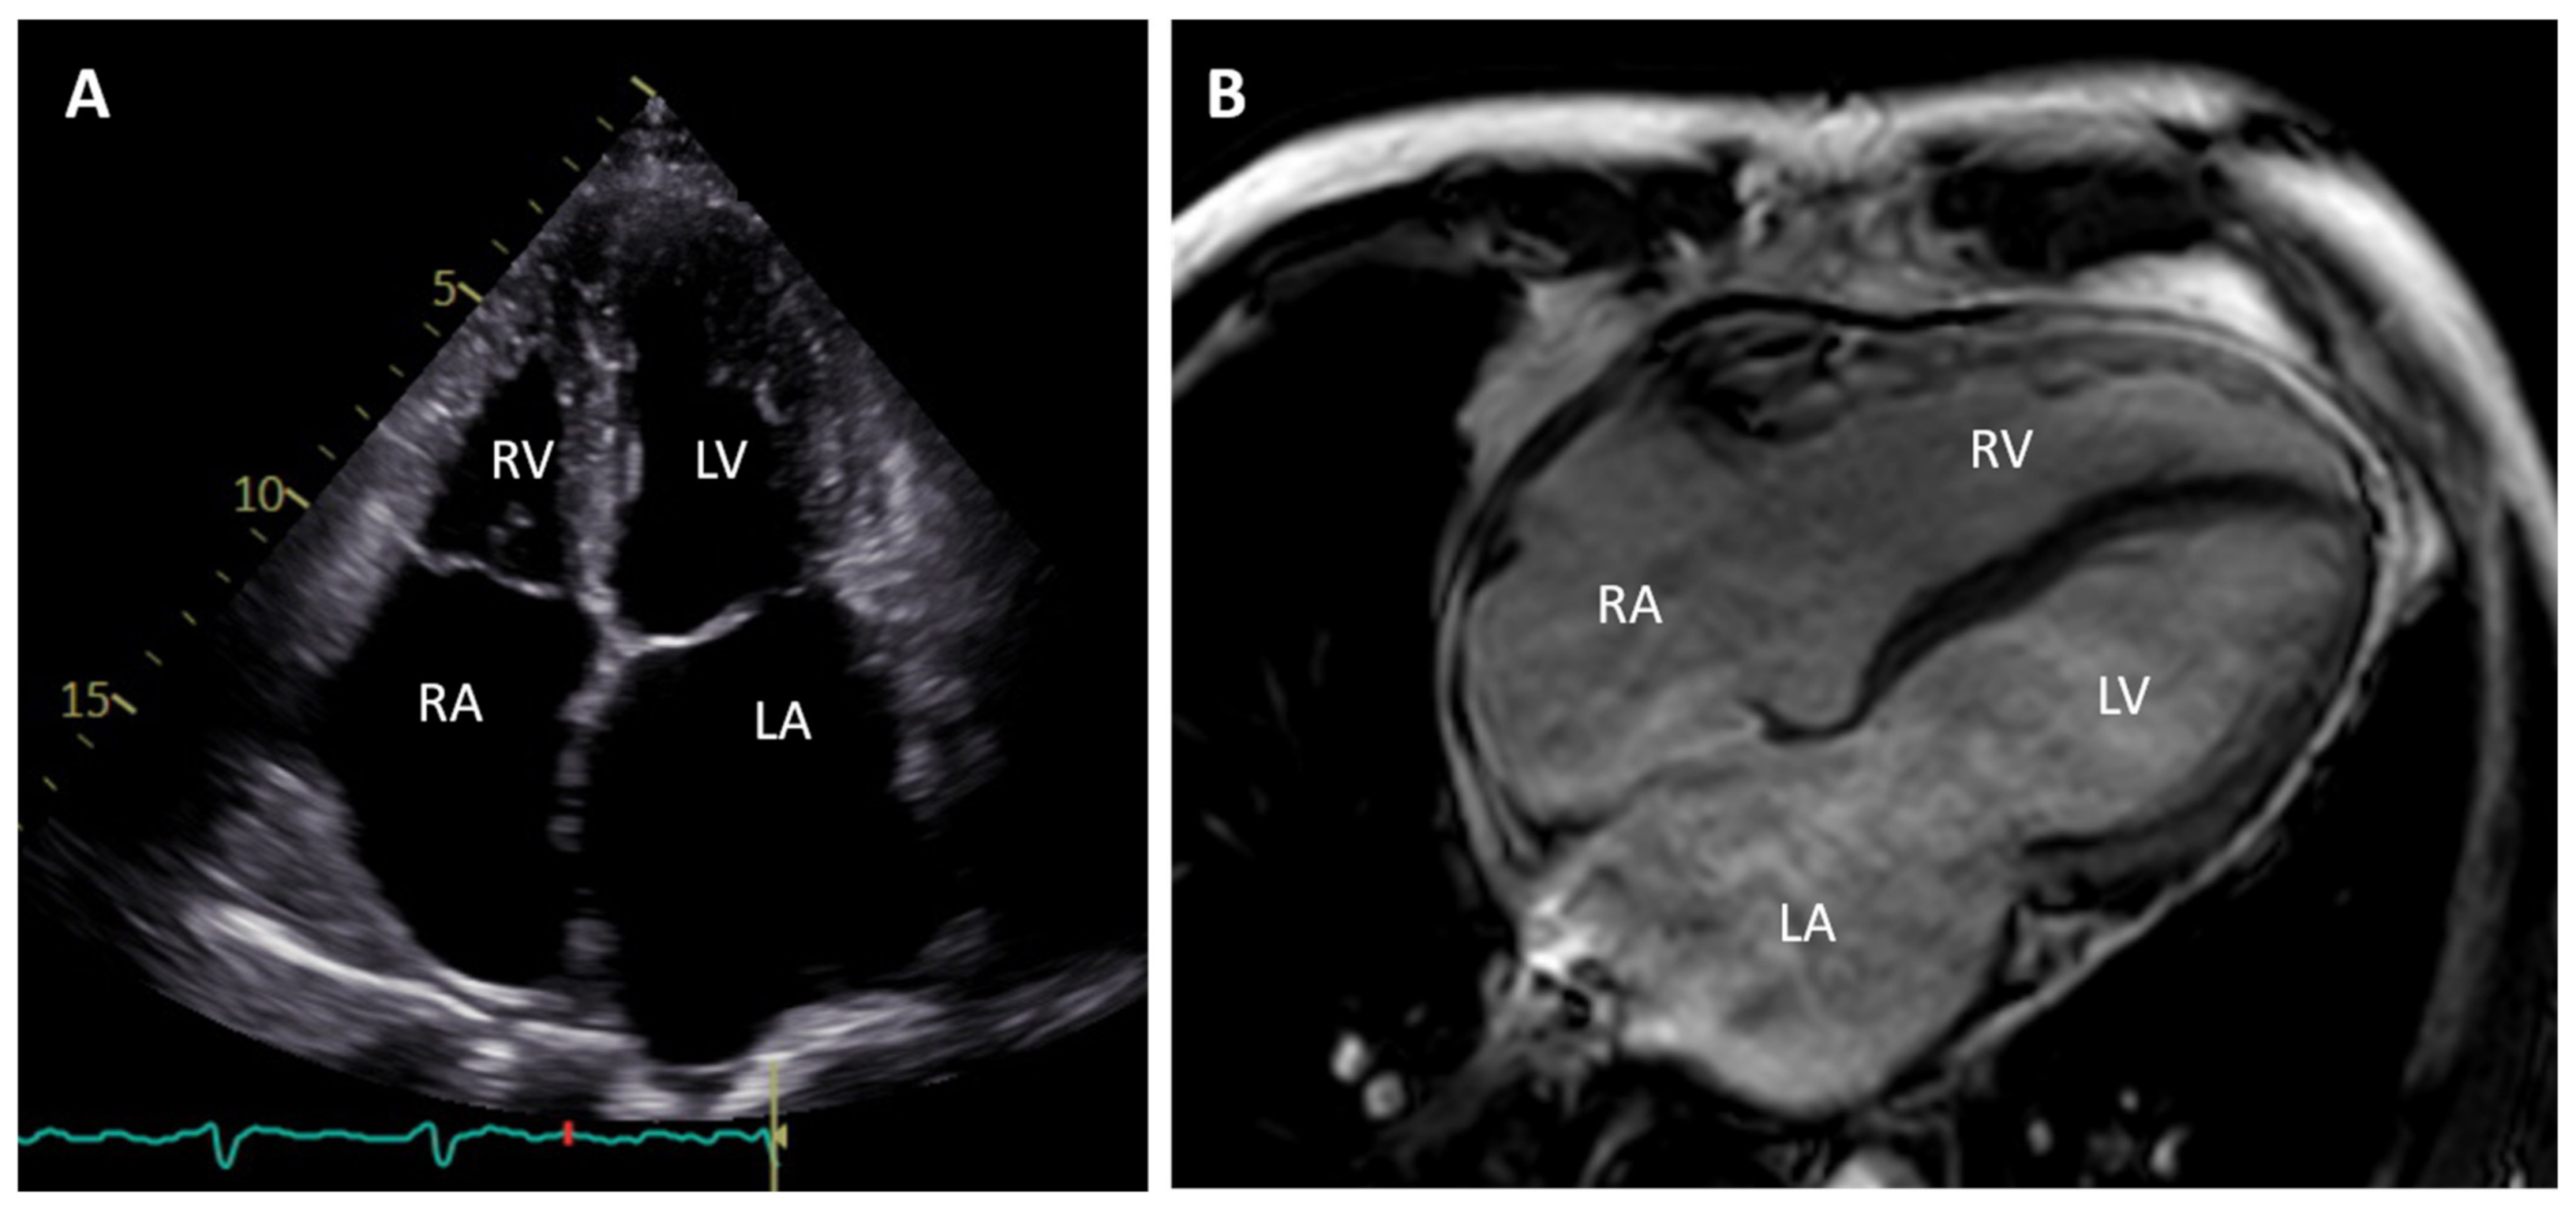

2. Clinical Description